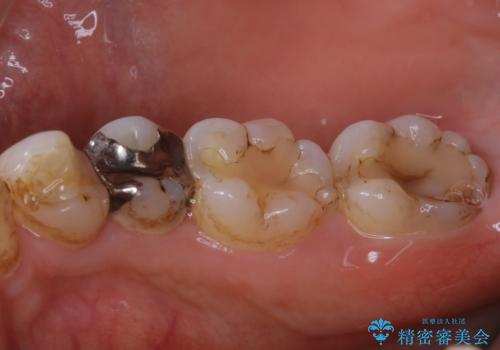

歯の表面に、茶色く色が残っている所がありますが、これは詰め物の変色の所と、虫歯になっている所です。以前に、CR(コンポジットレジン)による虫歯治療がされています。

CRは経年的劣化や、着色してしまうことがあります。PMTCでクリーニングを行うと、古いCRが目立つことがあるため、気になる際は詰め替えを行います。

茶色くなっている部分が、着色なのか、劣化なのか、虫歯によるものなのかは判別が難しいことがあります。そのため、定期的にPMTCを行うことで状態の確認が的確に行えます。